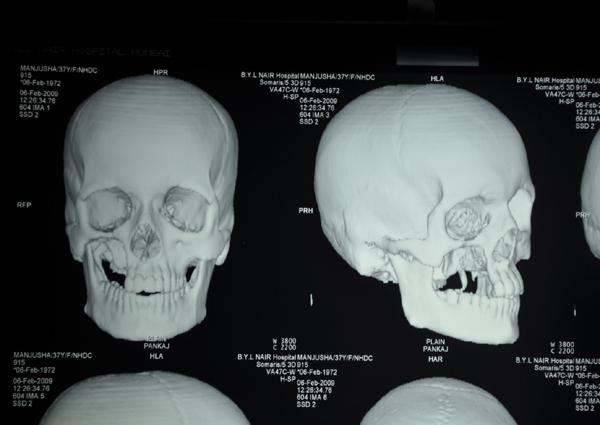

3 D RECONSTRUCTION SHOWS THE DEFECT IN MAXILLA